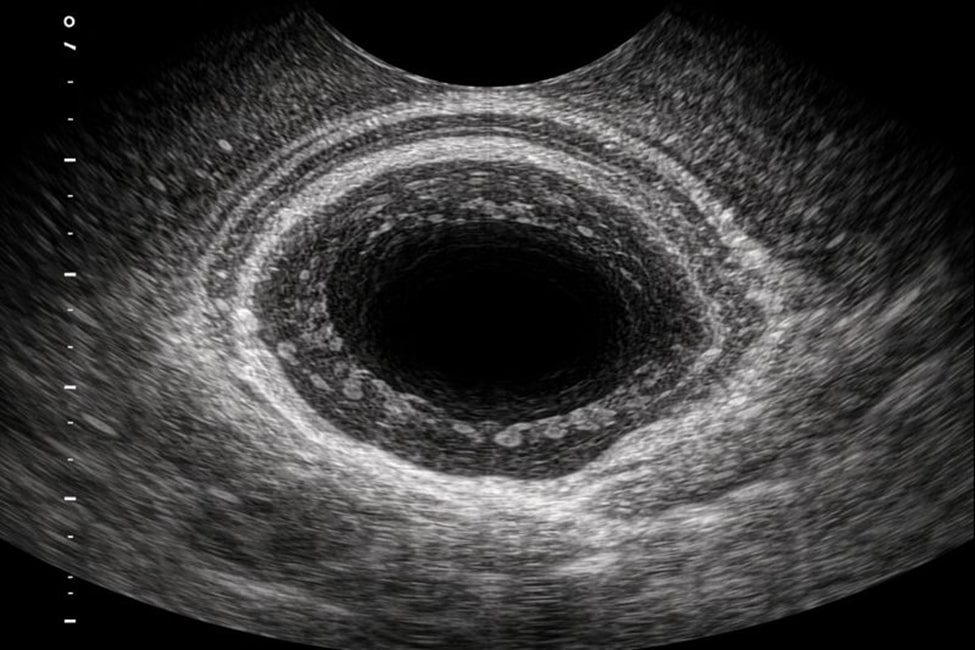

УЗИ прямой кишки представляет собой инструментальный ультразвуковой метод исследования, при котором визуализация осуществляется с использованием ректального доступа. Для этого применяется специализированный датчик, обеспечивающий детальное изображение внутренней структуры органа.

Данный вариант диагностики также известен как ТРУЗИ и активно используется в современной медицинской практике. Он позволяет оценить анатомические особенности, глубину поражений и состояние окружающих тканей. Метод дает возможность получить информацию, недоступную при поверхностных способах исследования.

УЗИ прямой кишки дает возможность детально оценить внутреннюю структуру органа, включая слизистую оболочку и подлежащую ткань. Врач анализирует толщину стенок, однородность структуры и наличие объемных образований.

Также ультразвуковое исследование прямой кишки информативно при комплексной оценке соседних анатомических зон. Могут изучаться предстательный отдел и прилегающая железа, что необходимо при диагностике заболеваний области, в которой расположена простата.

УЗИ прямой кишки проводится в условиях специализированного диагностического кабинета. Пациент занимает удобное положение, после чего ультразвуковой зонд аккуратно вводиться в анальный канал.

Процедура занимает небольшой промежуток времени и переносится удовлетворительно. В процессе обследования специалист может проводить дополнительные измерения и уточняющие манипуляции. Манипуляция не требует обезболивания и не сопровождается восстановительным периодом.